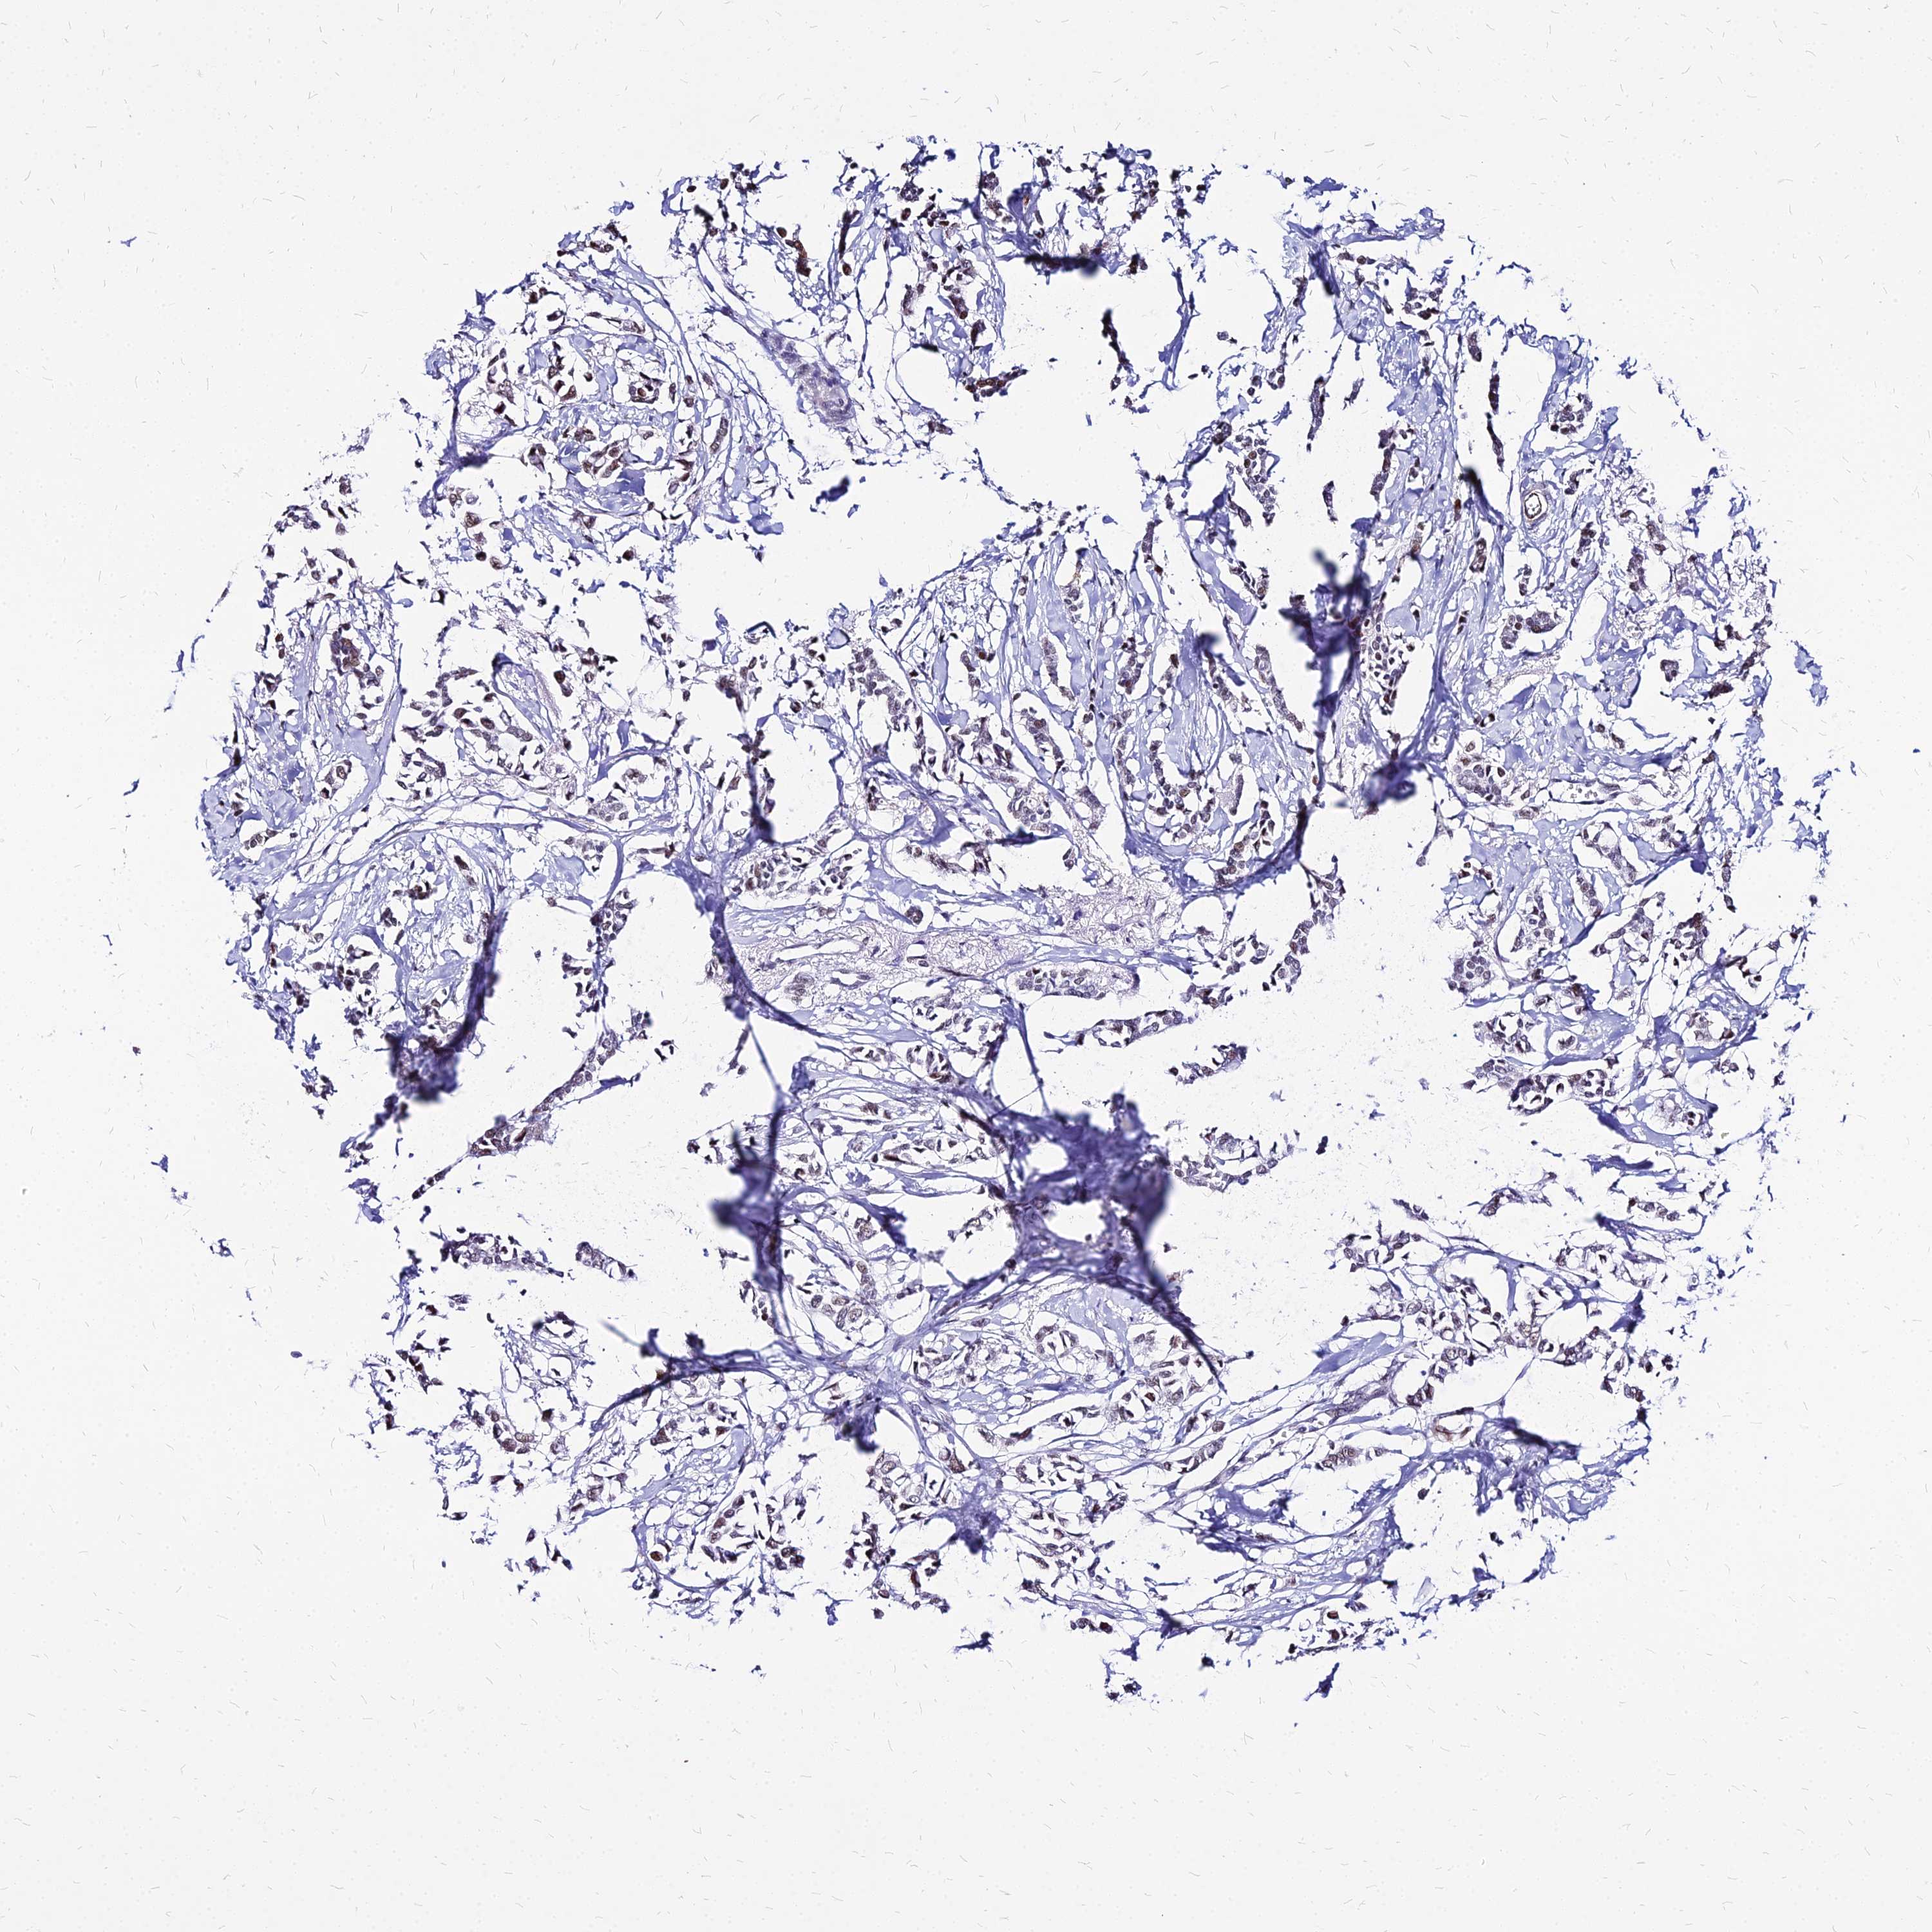

CANCER BREAST CANCER Show tissue menu

BRCA TCGA BRCA VALIDATION PROTEIN EXPRESSION

Breast cancer

Human cancer

Breast invasive carcinoma

FDX2 is not prognostic in Breast Invasive Carcinoma (TCGA)

TCGA RNA samplesi

RNA-seq data is reported as average FPKM (number Fragments Per Kilobase of exon per Million reads), generated by the The Cancer Genome Atlas (TCGA) .

Normal distribution across the dataset is visualized with box plots, shown as median and 25th and 75th percentiles. Points are displayed as outliers if they are above or below 1.5 times the interquartile range. FPKM values of the individual samples are presented next to the box plot.

Average pTPM 29.1

Number of samples 1022